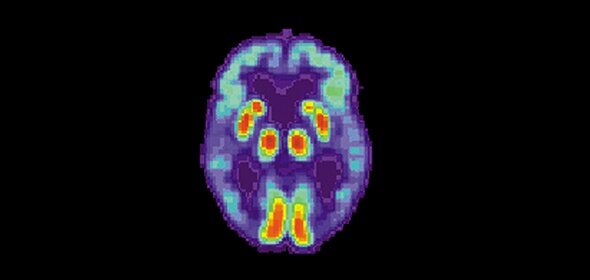

Картина ПЭТ-сканирования мозга пациента с болезнью Альйгеймера. Изображение phys.org.